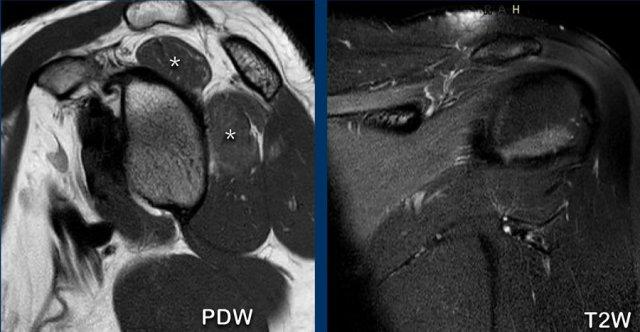

Rách gân dưới vai sau chấn thương trực tiếp.

Có hình ảnh co rút gân dưới vai về phía trước kèm phù nề quanh gân trên các chuỗi xung PD-weighted mặt phẳng axial và chuỗi xung T2W xóa mỡ mặt phẳng coronal (dấu hoa thị).

Gân cơ nhị đầu không bị trật (đầu mũi tên).

Bệnh nhân này có tiền sử chấn thương trực tiếp vùng khớp vai phía trước.